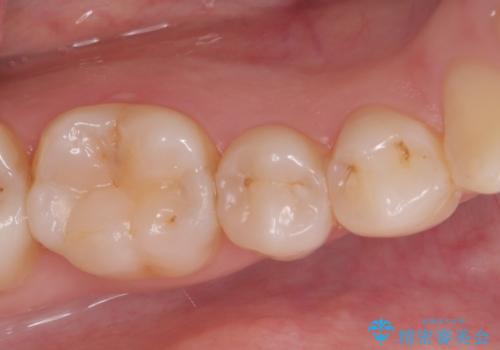

見落としやすい虫歯(コンタクトカリエス)を発見|精密診断で早期治療

- 患者様は特に痛みはなかったものの、定期検診で虫歯がないか確認したいとのことで来院されました。視診では明らかな虫歯は見当たりませんでしたが、レントゲン検査で歯と歯の間(コンタクトポイント)に虫歯(コンタクトカリエス)を発見。この部分の虫歯は初期では自覚症状が少なく、発見が遅れると治療範囲が広がることがあるため、早期に適切な治療を行う方針としました。